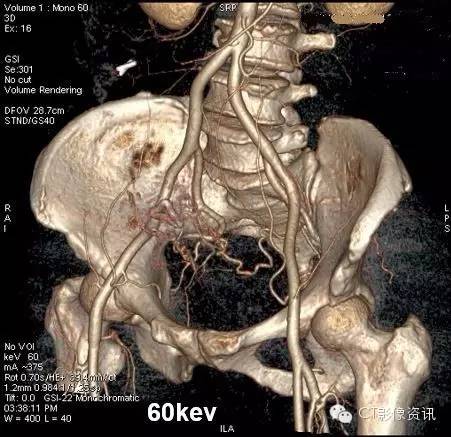

4、能谱单能量分析

单能量低keV,可以使原来难以结构清晰显示,为临床提供更多的病变信息。